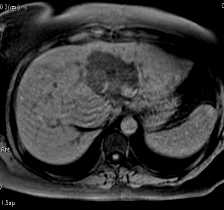

En T2 Haste l'angiomes du foie gauche est franchement en hypersignal et les contours sont polylobés. Le reste du foie est homogène. En EPI Diffusion la structure de l'angiome du segment II est bien visible et le parenchyme est un peu hétérogène dans le segment VII. En T1 EG L'angiomes est franchement en hyposignal le reste du foie est homogène